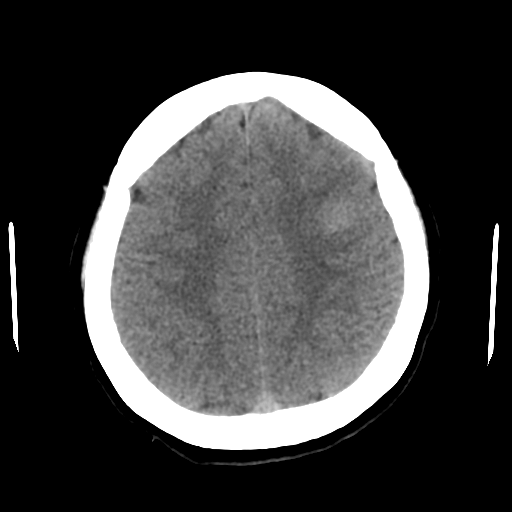

하지만 인공지능 프로그램은 여기서 이상을 찾아냈다!

바로 다음 처럼 말이다.

이렇게 인공지능이 이상하다고 생각하는 부분을 표시해주었고

다시 살펴보니 brain tumor나 focal한 SAH가능성이 있어보여 brain MR촬영을 하게 되었다. 그리고 뇌종양이 있음을 확인 할 수 있었다.

결과적으로 인공지능의 도움을 받아 놓칠 뻔한 뇌종양을 진단 했던 케이스였다.